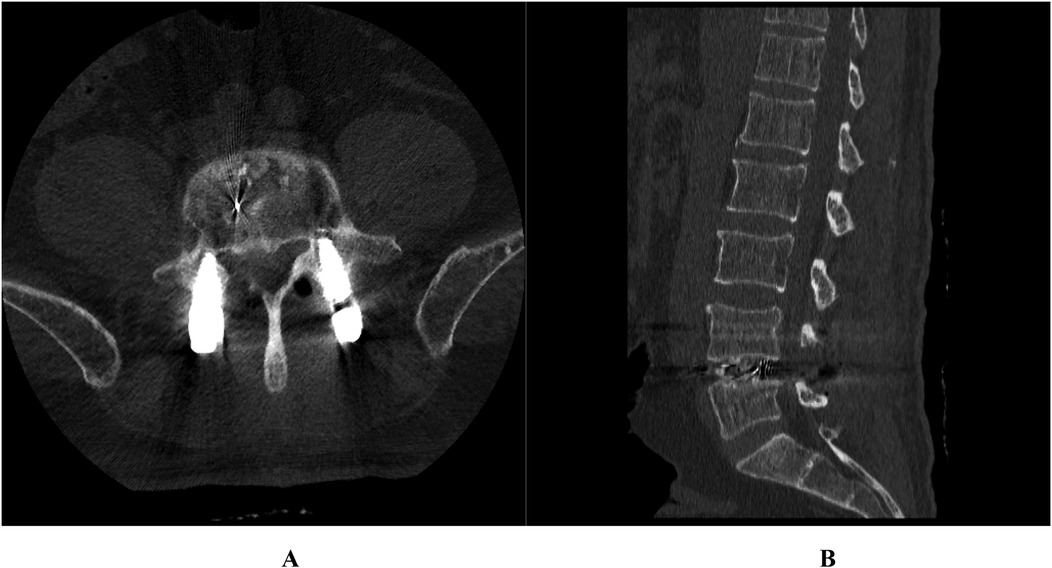

Posterior marginal osteophytes at the vertebral level are frequently observed in individuals with lumbar disc herniation (LDH); however, complete encasement of the nerve root by such osteophytes is exceedingly uncommon. We present two cases of surgical management of vertebral posterior marginal osteophytes completely encasing the nerve root. This report examined two cases of LDH accompanied by vertebral posterior marginal osteophytes completely encasing the nerve roots. Both patients underwent spinal canal decompression, discectomy, and intervertebral fusion. Postoperatively, varying degrees of nerve root injury were noted. By the 3-month follow-up, marked recovery in neurological function was achieved in both cases. The presence of vertebral posterior marginal osteophytes completely encasing the nerve root represents a notable risk factor for nerve root injury in LDH cases. Tailored surgical approaches are imperative to minimize complications and optimize patient outcomes.